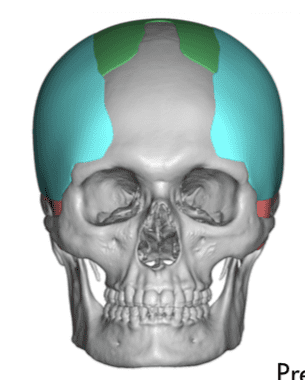

Desire for an improved head shape so that it looks rounder and not so peaked or sloped.

Placement of custom skull implant for parasagittal augmentation to create a rounder head shape. An example of what appears to be a high sagittal crest that is really low parasagittal skull areas.

Desire for head shape asymmetry improvement as the final stage of total skull reshaping surgeries. (previous skull implants are in green color)

Placement of custom temporal implant through an incision behind the ear.